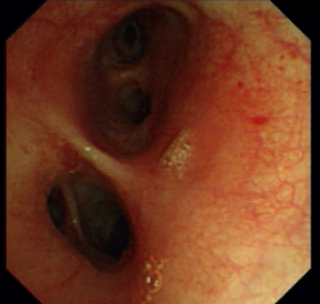

Once patients are suspected to have lung cancer or TB with X-ray or CT, bronchoscopy is followed-up from radiological imaging. Bronchoscopy is used as one of the invasive tool to directly detect the disease since 1960s [4]. Fig. 1 shows an example of normal tissue, TB and cancer. In bronchoscopy, usually we can observe that invasive TB, the lumen surface suffers from inflammatory change with hyperemia, edema and ulceration. Lung adenocarcinomas grow extraluminally and lead to lumen stenosis without affecting mucosal surface of lumen. Therefore, the mucosal surface of lumen is relatively smooth. However, squamous lung cancers always form intruding nodules and are difficult to be differentiated from TB granuloma visually. Computational aid is therefore needed in bronchoscopy, especially for lesion discrimination and targeting. Accurate targeting the disease area could significantly reduce the biopsy trauma and increase diagnostic accuracy [5].

Figure 1: A bronchoscopy image of normal (a), TB (b) and cancer (c)